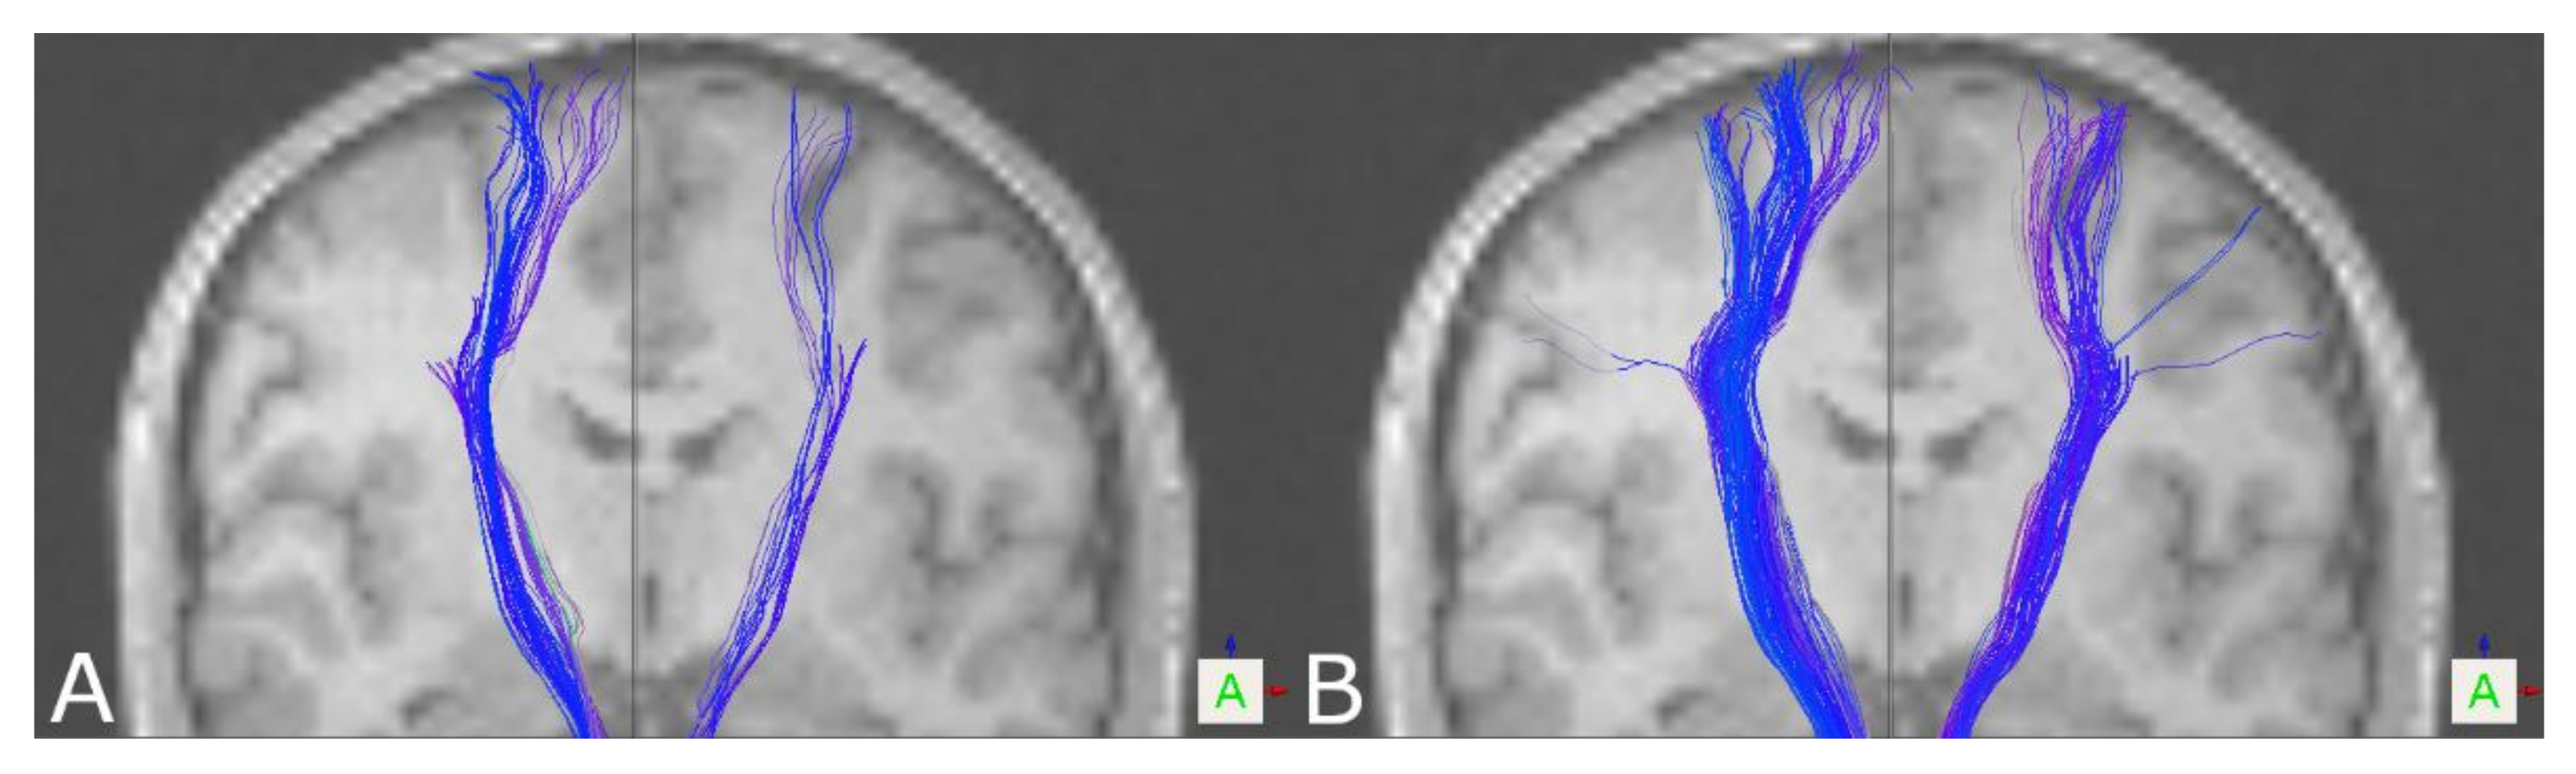

3.1. The Corticospinal Tract